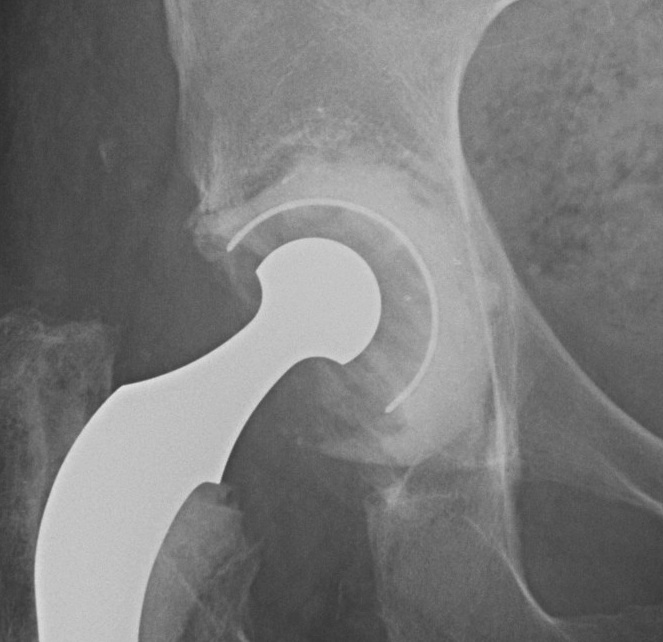

2. Impaction bone graft +/- mesh + cemented cup

Technique

1. If required, convert uncontained defect into contained defect

- use titanium mesh fixed with screws

- acetabular rim or medial wall mesh (Stryker)

2. Impact morcellised cancellous bone graft

- tamps or reverse reaming

- progressively smaller impactors

- need 5 mm of bone graft

3. Insert prosthesis / Cemented poly liner

Results

- 85% 12 year survival

- 80% 15 year survival

Important Points

1. Rigorous technique important

2. Fresh frozen allograft

- does this perform better than irradiated BG

3. TWB 6 – 12/52